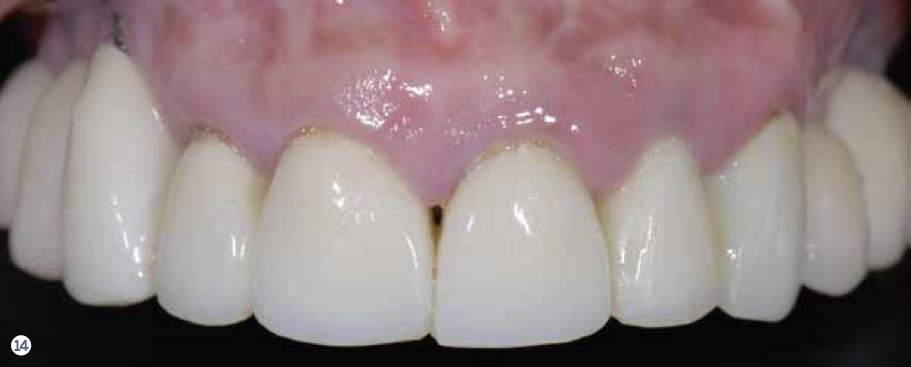

Fig 14 Pretreatment and posttreatment views of the implant-supported reconstruction. Notice the favorable changes in the gingival outline and tooth proportions.

Figure 14